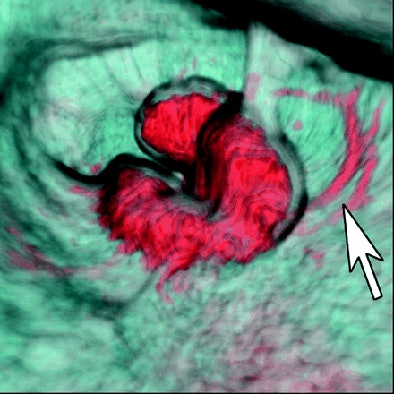

"First we adjusted the CT monitor's transparency and opacity setting to a value of 1 to display only the contour of the lumen and the mucosa," the team wrote. "Next, we adjusted the transparency and opacity setting to a value of 2 to display only the arterial-dominant blood with contrast medium. Third, we adjusted the spatial parameters to display only to a depth of 3 mm surrounding the lumen and the mucosa, which corresponds to the thickness of the intestinal wall. Fourth, we overlaid the data displayed in steps one through three to produce a surface and vascular view of the colorectal wall, and then we reduced the surface opacity to produce an obstructed vascular view."

| Above, colonoscopic view and surface and vascular virtual endoluminal images for representative case of advanced colorectal cancer in a 60-year-old woman. Colonoscopic view shows advanced cancer in sigmoid colon. Below, surface virtual endoluminal view in the same patient shows lesion. Bottom, vascular virtual endoluminal image clearly shows blood pooling of tumor and vessels. Iinuma G, Moriyama N, Satake M, Miyakawa K, Tateishi U, Uchiyama N, Akasu T, Fujii T, Kobayashi T, "Vascular Virtual Endoluminal Visualization of Invasive Colorectal Cancer on MDCT Colonography" (AJR 2005; 184:1194-1198). |

"This finding is especially noteworthy because among six advanced colorectal cancer lesions in patients without preparation, four (66.7%) were missed with the conventional surface approach, but all could be visualized on the vascular virtual endoluminal images," Iinuma and colleagues wrote.